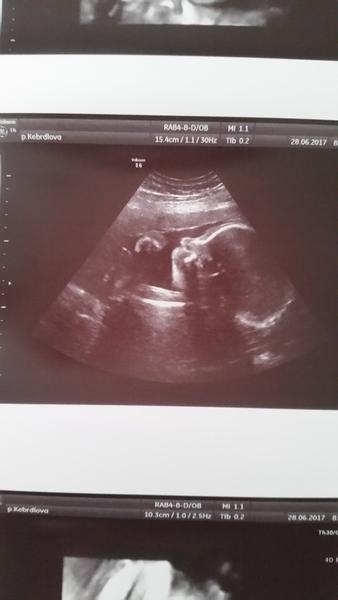

@pulguita tak je to za nami maly si daval rucicku pres oblicej ale neco se povedlo zachytit😉tak chlapecka nam nikdo neodpare je to na tuty😀vyfotila mu i pindika😀jdu pripravovat obed prijede ten pritele kolega a zacnou delat🙂to jsi dobra ze si vybehla a 5km za pul hodiny????tak to bych nedala ale ja az porodim tak chci taky zacit behat😀krasnou stredu

@petrysek181 To je kraaasna fotecka,aspon ze nee vsechny miminka nejsou jako to nase,co se proste neukaze a neukaze😂

@petrysek181 No ten je nádherný😍 Hezky jde vidět. Co na to přítel? Byl na měkko? 🙂

Krásnou středu a zarámuj si tu fotečku, opravdu se povedla🙂